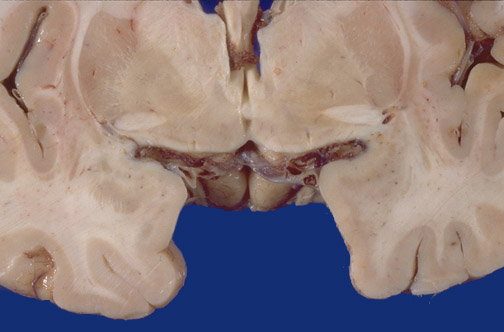

Identify the following regions of the brain on transverse section in the image above: Putamen - Globus Pallidus - Anterior Commissure - Nucleus Basalis of Meynert - Internal capsule - External capsule - Claustrum - Insular cortex